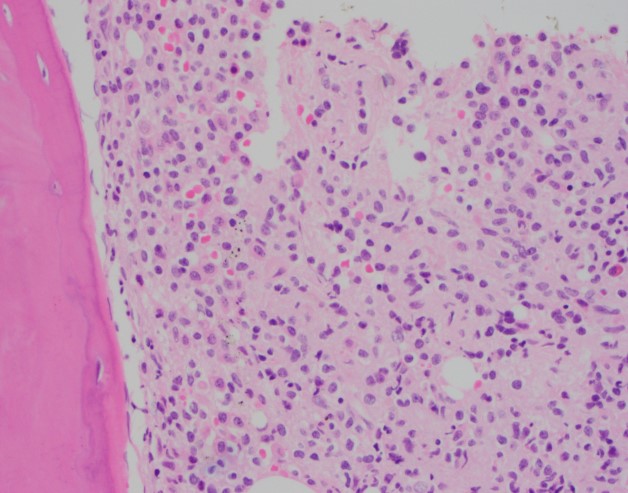

The core biopsy shows an infiltrating population of atypical lymphocytes with moderate amounts of pale eosinophilic cytoplasm and mature chromatin that stain positive for CD20. Frequent mononuclear cells consistent with plasma cells are also seen scattered throughout the bone marrow and stain positive for CD138.